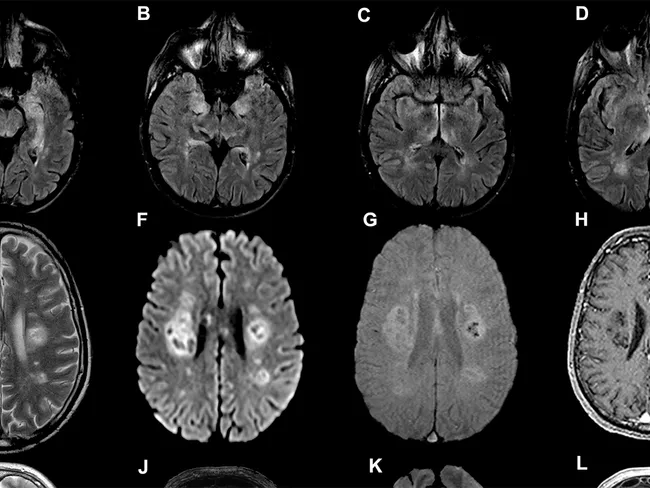

Persoanele care se recuperează după boala COVID-19 pot suferi efecte semnificative asupra funcției creierului, cele mai grave cazuri de infecție fiind legate de declinul mintal echivalent cu îmbătrânirea creierului cu zece ani, au avertizat cercetătorii britanici de la Imperial.

Un studiu care nu are evaluare internațională, pe mai mult de 84.000 de persoane, condus de Adam Hampshire, medic la Imperial College London, a constatat că, în unele cazuri severe, infecția cu coronavirus este legată de deficite cognitive substanțiale timp de luni de zile.

„Dacă cercetătorii vor vrea să înțeleagă mai bine impactul pe termen lung al COVID, va fi important să investigheze în continuare măsura în care este afectată funcția cognitivă în săptămânile și lunile de după infecție și dacă se produc leziuni permanente ca rezultat al bolii la unele persoane”, a subliniat Derek Hill, profesor de științe imagistice medicale la University College London.